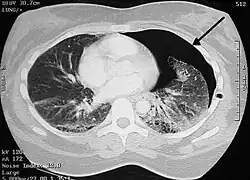

Pneumotórax

Pneumotórax (do grego, pneumo ar; thorax peitoral) é uma emergência médica causada pela presença de ar entre as membranas que envolvem os pulmões (cavidade pleural) e gera um pulmão colapsado (atelectasia) disfunção nos alvéolos, causada pelo extravasamento de líquido da pleura. Pode afetar um ou ambos pulmões e causar dificuldade para respirar (dispneia).[1]